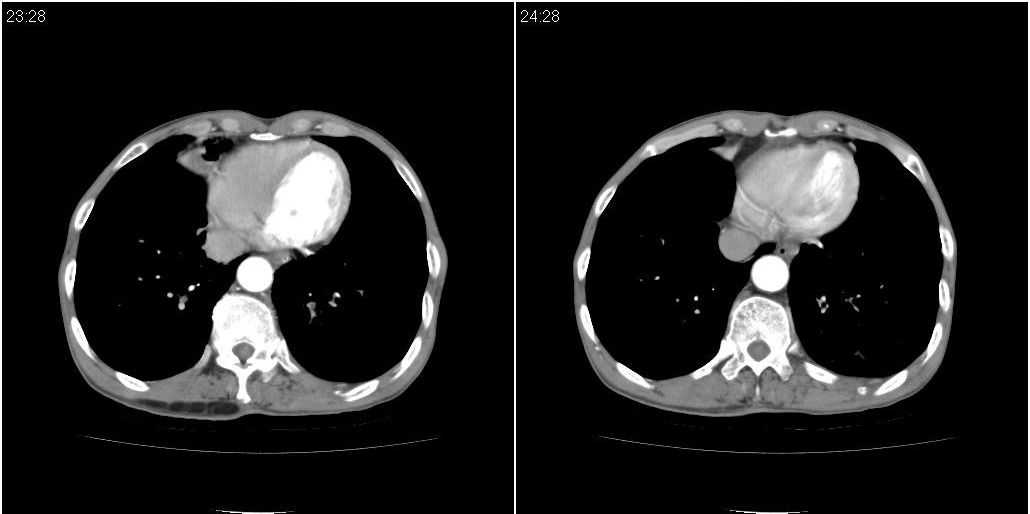

标题: CT25416:男性,70岁。胸片发现右下肺斑片状阴影

以下是ct检查的情况:

标题: ct增强:

右肺中叶阻塞性不张及肺炎,高度怀疑支气管占位,建议纤支镜检查!

1)右肺中叶慢性炎症并支气管扩张,节段性肺不张。2)两肺下叶支气管扩张。